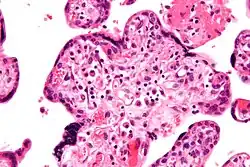

Задержка развития плода может требовать различных тактик ведения беременности и родов, в зависимости от причин болезни, степени её выраженности, формы и срока беременности[2]. Цель лечения — коррекция нарушений в системе мать-плацента-плод[2]. Повторные ультразвуковые кардиомониторные наблюдения необходимы для оценки темпов роста плода и его функционального состояния[2]. Помимо этого, рекомендовано генетическое тестирование[5] и мониторинг через фетальный доплер[6]. Если терапия даёт положительный результат, то беременность можно продлить. Родоразрешение проводят не ранее 37 недель беременности[2]. Если лечение неэффективно или состояние плода ухудшается, досрочное родоразрешение необходимо, независимо от срока беременности[2]. При декомпенсированной форме плацентарной недостаточности (ЗРП II и III степени) показано досрочное родоразрешение путем операции кесарева сечения[2]. После рождения ребёнка с задержкой развития плода плаценту взвешивают и осматривают, чтобы выявить возможные инфаркты, артериовенозные пороки и отложения фибрина, а также отправить плаценту в лабораторию патоморфологии для установления возможной причины задержки развития плода[2].